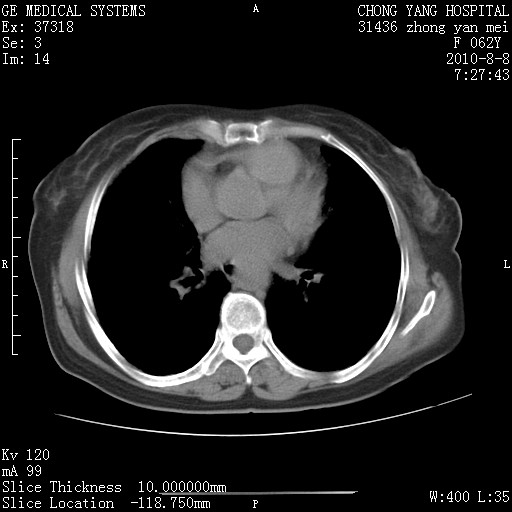

标题: CT28269:F62Y咳嗽胸痛数月。 [打印本页]

标题: CT28269:F62Y咳嗽胸痛数月。

另见右乳腺似有小钙化灶,建议进一步检查。

1.肺间质纤维化.

2.纵隔淋巴结肿大。

3.迷走右锁骨下动脉。

两肺间质改变,纵隔淋巴结肿大,需要考虑结节病的可能。